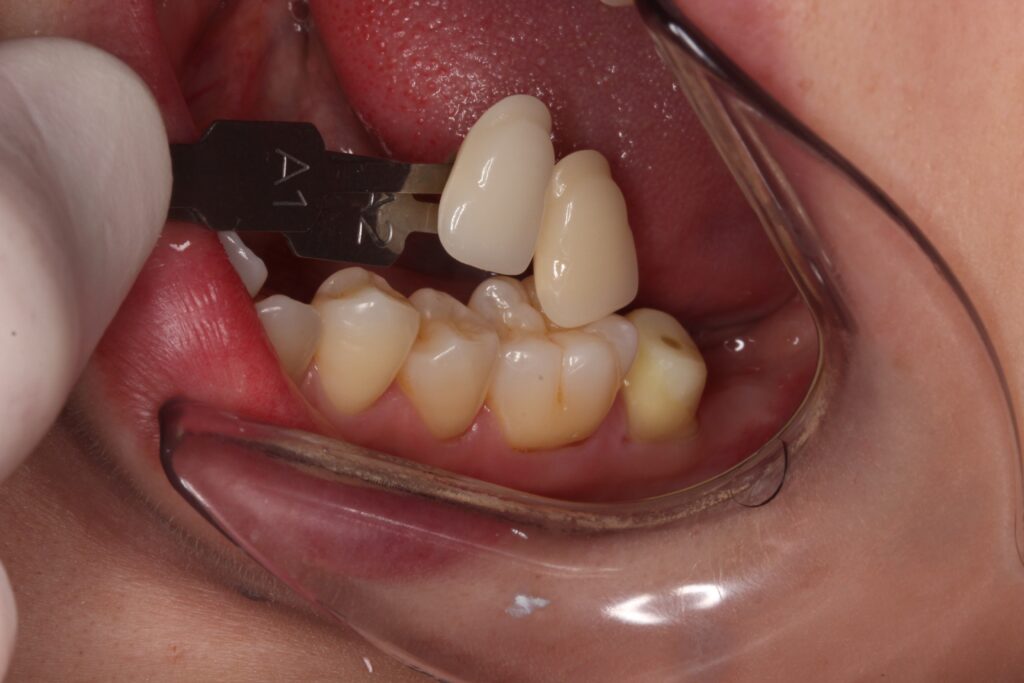

歯の色を記録して、セラミッククラウンを製作します。